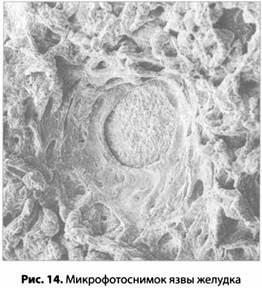

Язва

Наконец мы добрались до медицинской проблемы, с которой начался путь теории стресса к славе и богатству. Язва — это дыра в стенке органа (рис. 14). Если язва возникает в желудке или в окружающих его органах, это называется язвенной болезнью. Язву, возникшую в самом желудке, называют язвой желудка; язву, расположенную немного выше желудка, называют язвой пищевода, а если она возникла на границе между желудком и кишечником, ее называют язвой двенадцатиперстной кишки (или дуоденальной язвой). Это самое распространенное из всех язвенных заболеваний.